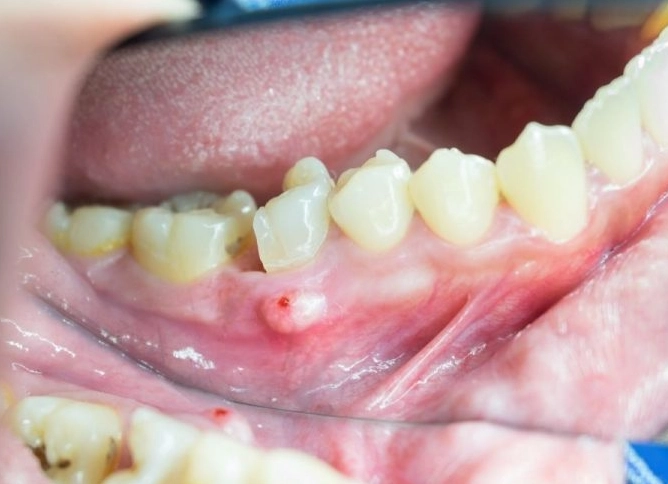

- It's getting bigger. Steady growth is a major warning sign.

- It's hard and fixed. If the lump feels rock-hard and you can't move it at all with your finger or tongue, that's concerning.

- It's ulcerated or bleeds easily. A lump that develops a crater in the middle or bleeds when you touch it (even gently) needs evaluation.